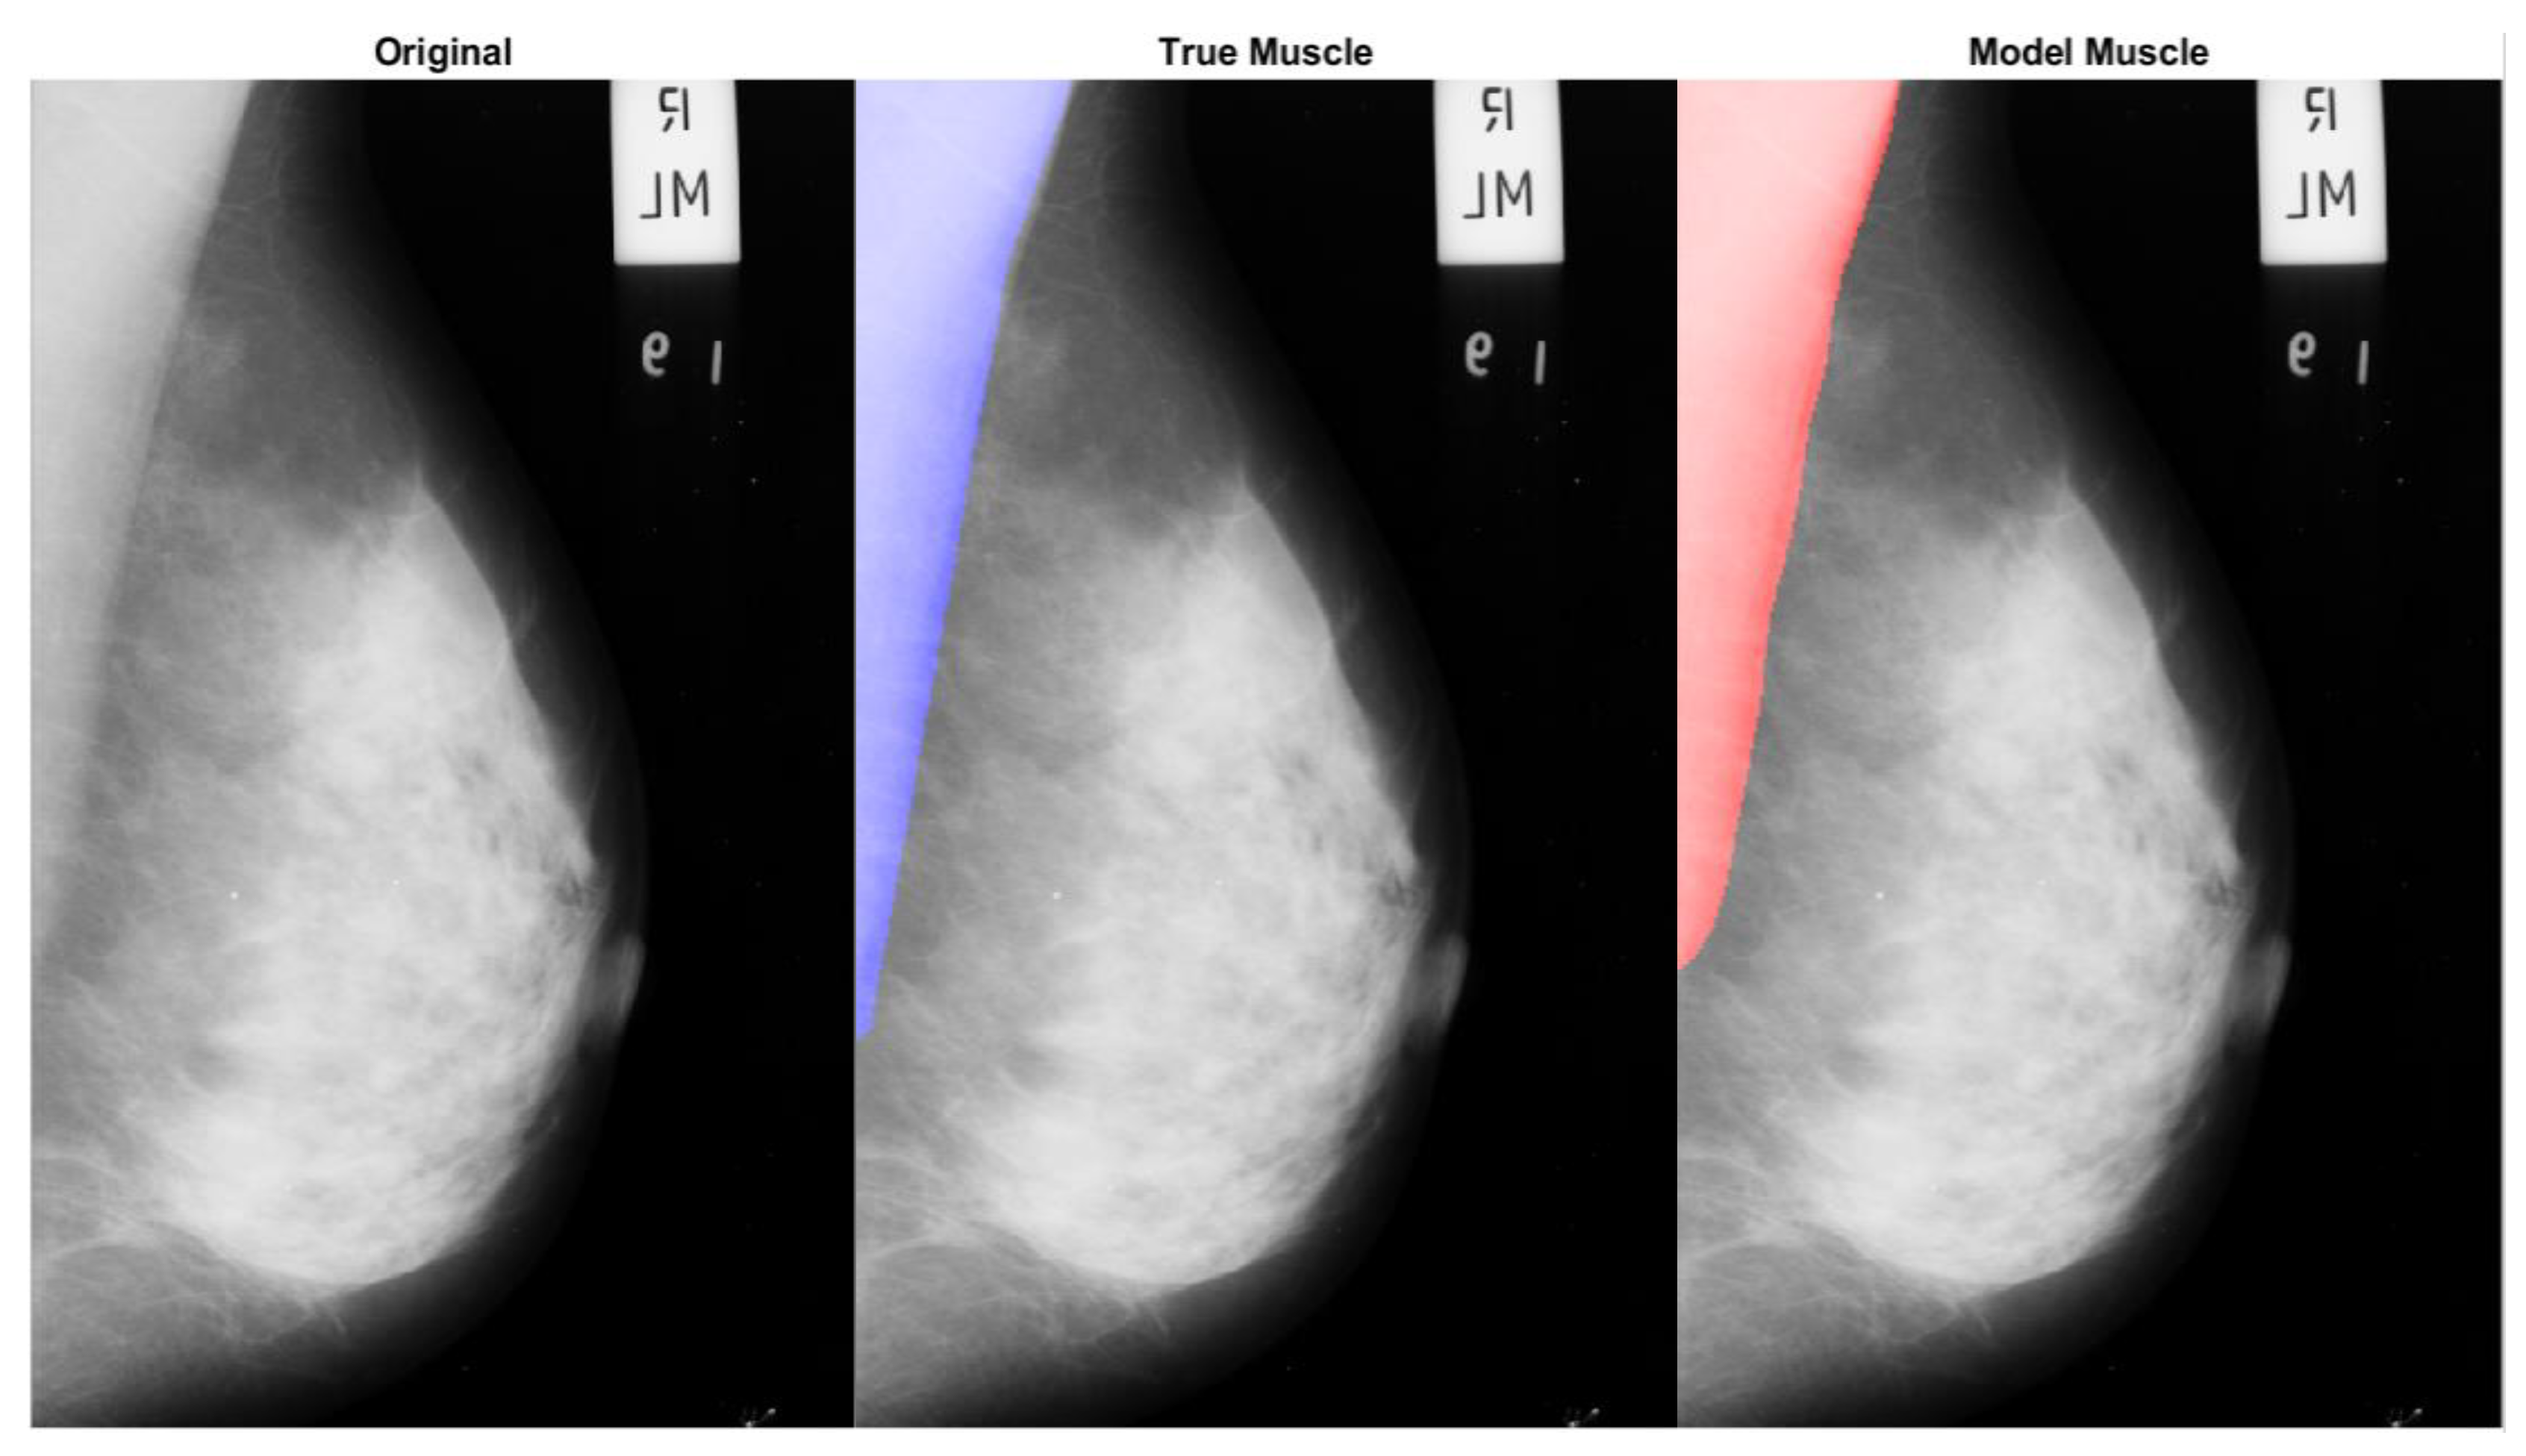

Figure 9 presents a comparative visualization of the original mammographic image, the ground truth muscle segmentation, and the muscle segmentation as identified by our CNN model. In the ‘True Muscle’ panel, the blue overlay indicates the expert-annotated region delineating the true muscle area, serving as a reference standard for segmentation. The ‘Model Muscle’ presents a red overlay which represents the muscle region as segmented by our CNN model, demonstrating the model’s ability to closely replicate the true segmentation.

Figure 9. Comparative visualization of mammogram segmentation, featuring the original image alongside the ground truth and automated model segmentations of the pectoral muscle. The original mammogram is displayed on the left, with the ground truth segmentation overlaid in blue at the center, and the model’s segmentation is overlaid in red on the right. This figure illustrates the model’s capability to identify the pectoral muscle against the expert-delineated ground truth, providing a concise evaluation of segmentation accuracy.